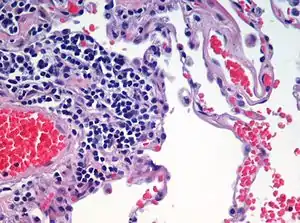

Histopathology is the branch of histology that includes the microscopic identification and study of diseased tissue.[5][6] It is an important part of anatomical pathology and surgical pathology, as accurate diagnosis of cancer and other diseases often requires histopathological examination of tissue samples.[10] Trained physicians, frequently licensed pathologists, perform histopathological examination and provide diagnostic information based on their observations.

Staining

Biological tissue has little inherent contrast in either the light or electron microscope.[17] Staining is employed to give both contrast to the tissue as well as highlighting particular features of interest. When the stain is used to target a specific chemical component of the tissue (and not the general structure), the term histochemistry is used.[9]

Light microscopy

Hematoxylin and eosin (H&E stain) is one of the most commonly used stains in histology to show the general structure of the tissue.[9][20] Hematoxylin stains cell nuclei blue; eosin, an acidic dye, stains the cytoplasm and other tissues in different stains of pink.[9][12]